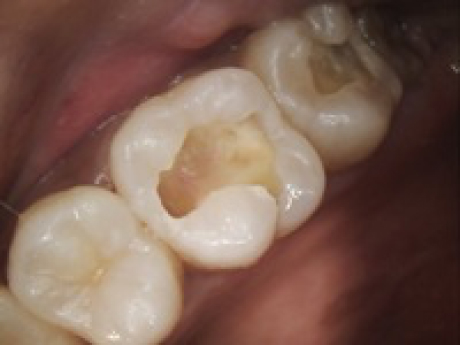

case3